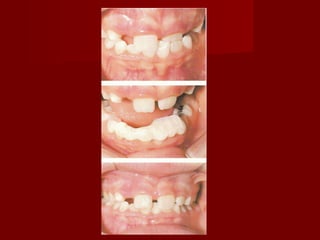

Anterior CrossbiteAnterior Crossbite

 A deviation from the normalA deviation from the normal

labio-lingual relationship of the teeth oflabio-lingual relationship of the teeth of

one archone arch

with those of the opposing arch.with those of the opposing arch.

DiagnosisDiagnosis

– Differentiate skeletal from non-skeletalDifferentiate skeletal from non-skeletal

problemproblem

Examination ??Examination ??

 Profile viewProfile view

 Skeletal pattern I vs IIISkeletal pattern I vs III

Cephalometric analysis ??Cephalometric analysis ??

 ANB ??ANB ??

 Wits ??Wits ??